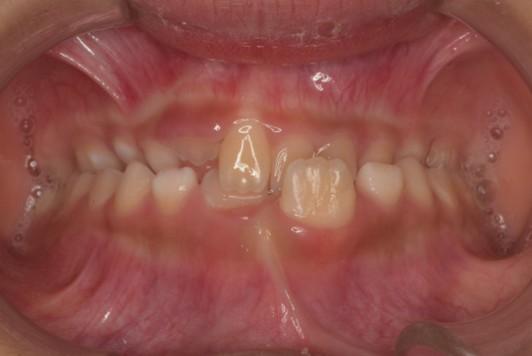

「叢生」は、一般的に「乱ぐい歯(らんぐいば)」「八重歯(やえば)」「ガタガタの歯並び」などと呼ばれる状態で、日本人に非常によく見られる不正咬合(ふせいこうごう:良くない噛み合わせ)です。

<叢生の状態>

顎(あご)の骨の大きさに対して、歯のサイズが大きすぎたり、歯が並ぶスペースが不足していたりするために、歯がデコボコに重なり合って生えている状態を指します。